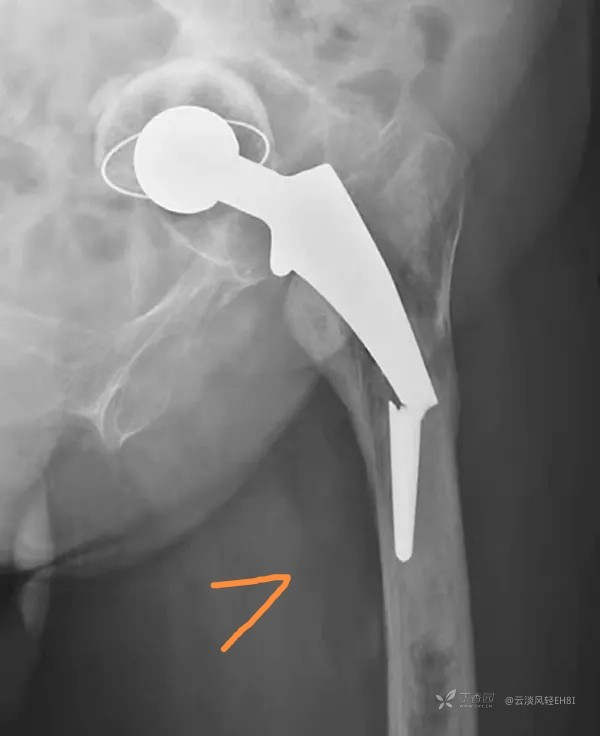

七、假体的变形和断裂(图7)

变形和断裂大多数出现于假体柄,大多数并且发生在术后数年或较长时期的载荷之后,但也有早期发生者。假体的失败通常是机械性和技术上的问题造成。如为早期发生失败,不排除是由于假体的材料加工存在问题。不锈钢材料所制假体柄,常先出现变形后再断裂,其他一些硬度较高的合金假体柄往往是疲劳断裂而无变形阶段。按失败发生率的高低,部位顺序是:柄的中1/3、近1/3和远侧1/3。引起失败的较公认原因是柄的近侧1/3缺乏骨水泥和骨组织的支托,使假体柄长期遭受悬臂力的作用,最终出现疲劳断裂。一般情况下,假体柄完全断裂时,会立即出现剧烈疼痛,负重时加重。当变形和不完全断裂时,或完全断裂,但近1/3仍有骨组织和骨水泥很好地支托时,患者可以完全无症状,或为轻微不适感。X线检查对此合并症的诊断非常重要,完全或不完全断裂很容易诊断,而变形只有依靠定期随访的X线片相互比较才能发现。